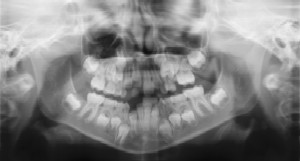

Dental Radiographs (X-Rays) Radiographs (X-Rays) are a vital and necessary part of your child’s dental diagnostic process. Without them, certain dental conditions can and will be missed.

Radiographs detect much more than cavities. For example, radiographs may be needed to survey erupting teeth, diagnose bone diseases, evaluate the results of an injury, or plan orthodontic treatment. Radiographs allow dentists to diagnose and treat health conditions that cannot be detected during a clinical examination. If dental problems are found and treated early, dental care is more comfortable for your child and more affordable for you.

The American Academy of Pediatric Dentistry recommends radiographs and examinations every six months for children with a high risk of tooth decay. On average, most pediatric dentists request radiographs approximately once a year. Approximately every 3 years, it is a good idea to obtain a complete set of radiographs, either a panoramic and bitewings or periapicals and bitewings.

Pediatric dentists are particularly careful to minimize the exposure of their patients to radiation. With contemporary safeguards, the amount of radiation received in a dental X-ray examination is extremely small. The risk is negligible. In fact, the dental radiographs represent a far smaller risk than an undetected and untreated dental problem. Lead body aprons and shields will protect your child. Today’s equipment filters out unnecessary x-rays and restricts the x-ray beam to the area of interest. High-speed film and proper shielding assure that your child receives a minimal amount of radiation exposure.